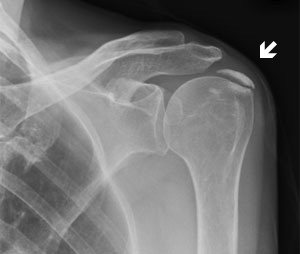

- Plain films will show calcification in the tendon(s) of the rotator cuff

- Note: calcification is not specific for calcific tendinitis (may occur in asymptomatic patients)